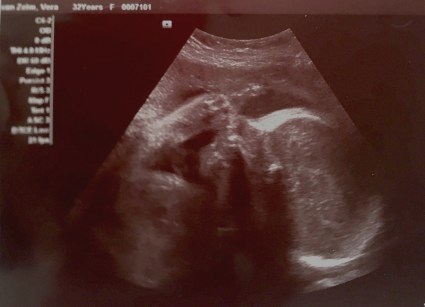

Ik ben heel blij dat we een baby krijgen, denk ik, want ik begon te huilen toen ik een hartje zag op het echo scherm. Maar ondanks dat gegeven voel ik me niet goed. Ik voel me raar.

Ik doe mee aan een onderzoek. Daarom krijg ik een extra echo bij 28 weken. Dat is natuurlijk voornamelijk leuk. Dan kan ik hem weer even zien. Tijdens de echo is alles goed. Hij blijkt zelfs eerder aan de grote kant dan aan de kleine. Hij is dus nog niet te klein “doordat je pillen slikt”, of klein door “depressie”. Dat vind ik goed nieuws.

Maar gelukkig. De band tussen en moeder en kind blijkt inderdaad sterk. Mijn baby steekt zijn middelvinger op. Duidelijk zichtbaar op het scherm. Ik ben trots.